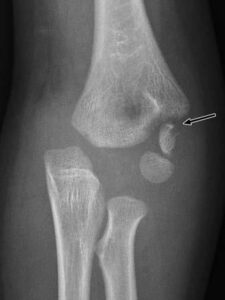

[toggle title=”Medial Epikondiler Kırıklar” state=”close”]

Çoğunlukla 10-14 yaş arası çocuklarda görülür.

Yaralanma direkt travma sonucu olabileceği gibi fleksör kas grubunun oluşturduğu avülsiyon sonucu ya da dirsek çıkığına sekonder de olabilir.

Medial epikondil kırıklarının yarısına yakınında eşlik eden dirsek çıkığı da görülür. Bu hastalarda dirsek redükte edildiğinde medial epikondil kırığı da redükte olur.

Kırık parçanın eklem içinde kalması nedeniyle redüksiyon yapılamayan durumlarda ya da kırığa eşlik eden ulnar sinir yaralanması varlığında cerrahi tedavi gerekir.